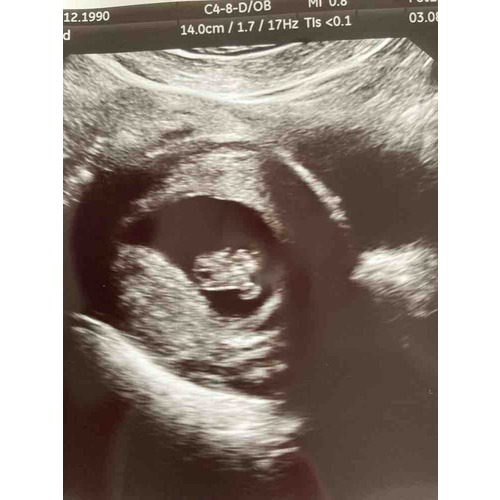

Haii hier was ik 8+3 Je ziet een klein beetje de stompjes waar de armpjes komen en links zijn de billetjes 馃槂 Het is zo bijzonder en mooi om al zo鈥檔 klein hartje te zien kloppen 馃グ